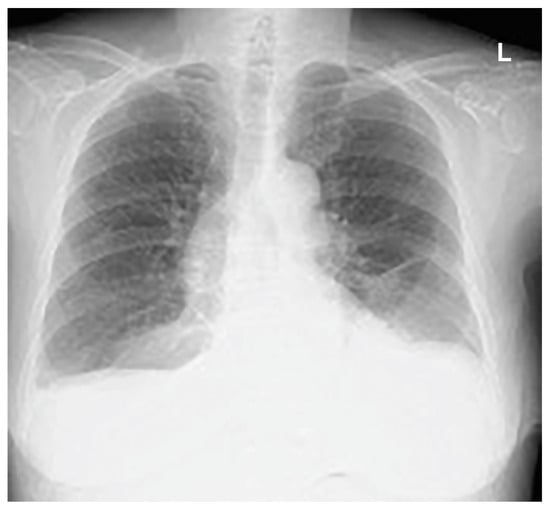

The following day, the subcutaneous emphysema showed a trend of enlargement on the chest X-ray image. Therefore, an additional drain (20 Fr) was placed from the left anterior thoracic region into the left thoracic cavity (Figure 4).

Figure 4.

An additional drain (20 Fr) was placed from the left anterior chest to the left thoracic cavity.